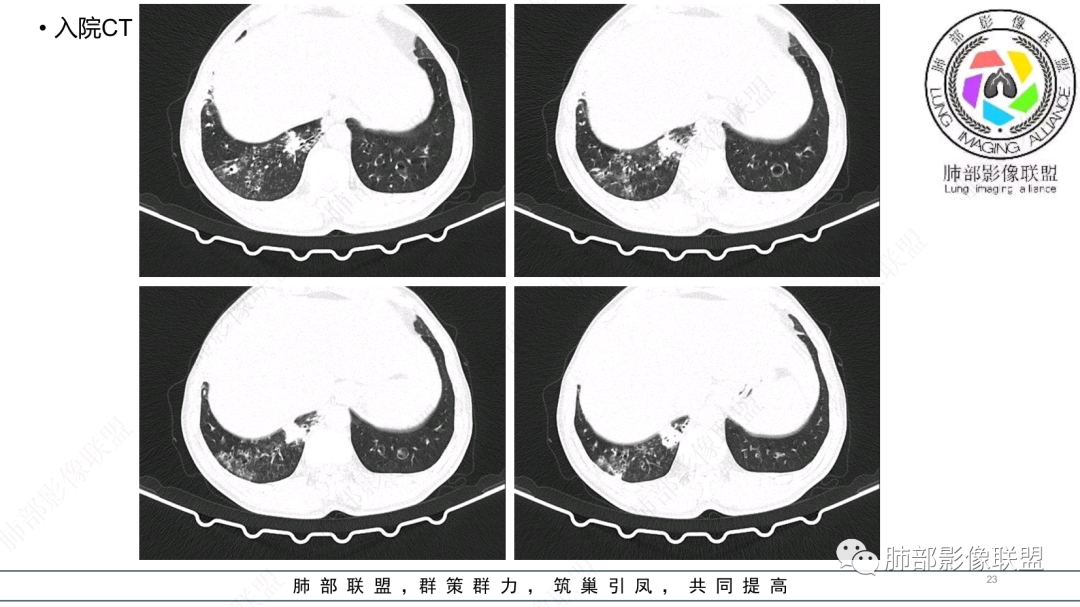

男性,56岁,清洁工,临床表现咳嗽咳痰发热。胸部影像:两肺散在斑片、结节及实变影,大部分沿气道分布,以下肺为著并伴发多发支气管扩张及囊腔影,实验室检查白细胞增高,考虑感染性病变,曲霉、铜绿及NTM。

56岁,工作性质:环卫工人。主诉:咳、痰、喘、发病一周。急性起病(或者慢病+AE),呼吸道感染症状。化验指标白细胞、中性、CRP明显升高。影像学显示多灶性,有柱状支扩,囊状支扩等结构肺病,责任细菌主要考虑铜绿假单胞菌,不排除合并其他细菌以阴杆为主;存在树芽影,发热,炎症沿支气管束分布,是否合并TB?真菌?;树芽伴发热支原体感染也要需要考虑进去;全肺多灶性炎症,部分病灶周围有晕,右上叶疑似反晕,内部疑似有丝,右下肺考虑存在粘液栓,加之环卫工工作性质,考虑霉菌,主要考虑曲霉。

影像改变为支扩伴气道来源感染,部分实变性伴有小脓肿及钙化,结合PCT及白细胞、中性粒明显增高,符合细菌感染,首先考虑奴卡,绿脓次之,因为临床有喘息、影像实变性有钙化,加上环卫工这一职业史,需要鉴别曲霉或奴卡合并曲霉。

(3)空洞:因病变是化脓性感染,病灶坏死排出,空洞较常见。          (4)累及胸膜及胸壁可形成胸腔积液、脓胸。